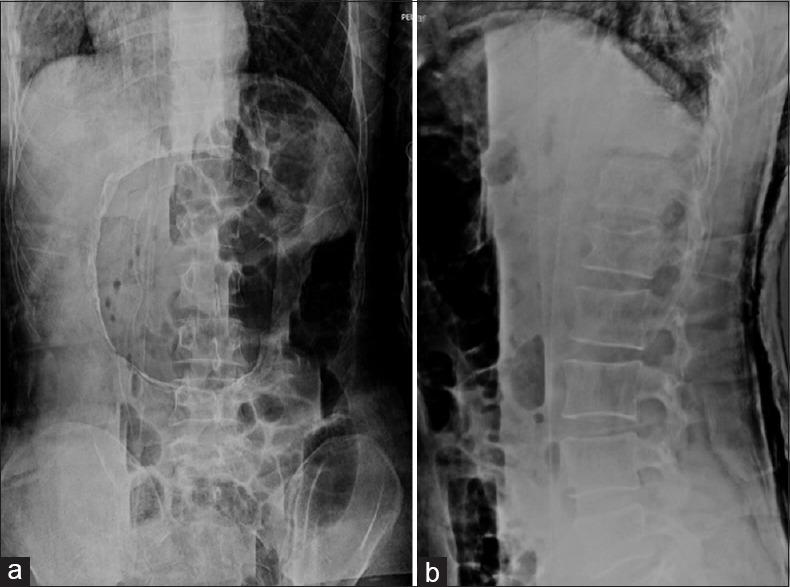

Thoracolumbar vertebral fractures are common in high-energy trauma and often are associated to other concomitant injuries. Currently, brace and Closed Reduction and Casting (CRC) are the two conservative treatments proposed by literature. Despite CRC was widely used in the past, today brace is preferred. The aim of our study is to evaluate clinical and radiographic outcomes of thoracolumbar type A fractures, not associated with other injuries, treated with CRC.

MATERIALS AND METHODS

We retrospectively evaluated all patients treated from 2008 to 2015, with a mean age of 26.69 years (range 15-45). All patients were affected by AO type A fracture: 26 type A1, 17 type A2, and 21 type A3. All patients were evaluated by X-ray, computed tomography, and magnetic resonance imaging. Radiological evaluations included vertebral kyphosis (VK), segmental kyphosis (SK), regional kyphosis (RK) angle, and vertebral ratio (VR) measures. Patients were clinically assessed through visual analog scale, Oswestry Disability Index, Roland-Morris Disability Questionnaire, and Short Form 36 Health Survey.

RESULTS

Seventy-four patients (41 males and 33 females) were included in the study. At follow-up (mean 28.48 months ± 5.16), we found significant improvements in VK ( = 0.000013), SK ( = 0.000455), and RK ( = 0.000016). No significant differences were observed in VR ( = 0.26). Good clinical results were reported in patients in all scores and 90.7% of patients returned to work.

CONCLUSIONS

Closed reduction and casting is still a reliable treatment option in selected thoracolumbar fractures without spinal cord involvement. A correct fracture evaluation, patient compliance, and motivation are essentials.

胸腰椎椎体骨折在高能创伤中很常见,且常伴有其他合并伤。目前,支具和闭合复位与石膏固定(CRC)是文献中提出的两种保守治疗方法。尽管CRC过去被广泛使用,但如今支具更受青睐。我们研究的目的是评估采用CRC治疗的、不伴有其他损伤的胸腰椎A型骨折的临床和影像学结果。

材料与方法

我们回顾性评估了2008年至2015年期间治疗的所有患者,平均年龄为26.69岁(范围15 - 45岁)。所有患者均为AO型A型骨折:26例A1型、17例A2型和21例A3型。所有患者均接受了X线、计算机断层扫描和磁共振成像检查。影像学评估包括椎体后凸(VK)、节段性后凸(SK)、区域后凸(RK)角和椎体比率(VR)测量。通过视觉模拟量表、Oswestry功能障碍指数、Roland - Morris功能障碍问卷和简短健康调查问卷对患者进行临床评估。

结果

74例患者(41例男性和33例女性)纳入研究。在随访时(平均28.48个月±5.16),我们发现VK( = 0.000013)、SK( = 0.000455)和RK( = 0.000016)有显著改善。VR方面未观察到显著差异( = 0.26)。所有评分的患者均报告了良好的临床结果,90.7%的患者恢复工作。

结论

闭合复位与石膏固定在选定的无脊髓受累的胸腰椎骨折中仍是一种可靠的治疗选择。正确的骨折评估、患者的依从性和积极性至关重要。